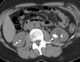

Renal calculi in hydronephrosis

Hydronephrosis describes hydrostatic dilation of the renal pelvis and calyces as a result of obstruction to urine flow downstream. Alternatively, hydroureter describes the dilation of the ureter, and hydronephroureter describes the dilation of the entire upper urinary tract (both the renal pelvicalyceal system and the ureter). [Source: Wikipedia ]